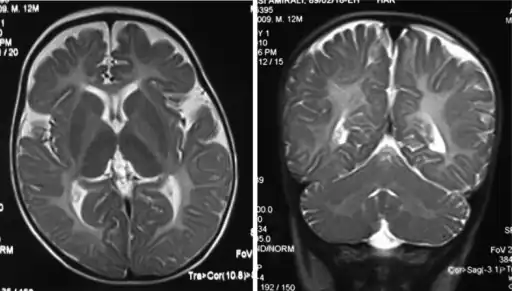

The diagnosis of Pelizaeus–Merzbacher disease is often first suggested after identification by magnetic resonance imaging of abnormal white matter (high T2 signal intensity, i.e. T2 lengthening) throughout the brain, which is typically evident by about 1 year of age, but more subtle abnormalities should be evident during infancy.

- Iso intensity in bilateral periventricular deep white matter

- Left- MRI,abnormal high signal internal capsule,Right MRI,high signal white matter of cerebellum